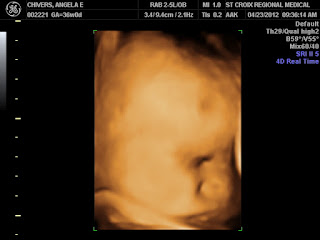

Drew at 33 weeks gestation

Looking back at Drew's last ultrasound it is amazing how much he looked like this baby. Same pudgy lips, round nose, and little chin. We miss you baby Drew.

We didn't do weight estimates at week 34, but we were able to get a lot of amazing pictures. Baby was sucking his fingers, swallowing, and it even looks like he is smiling in some of the pics.

35 Weeks, Monday, April 16, 2012

Today we decided to do an amniocentesis on the morning of April 30, when I will be 37 weeks. The test will be sent out and the results should be back by six or seven that evening. If his lungs are mature, we can induce that evening. We are hoping and praying for beautiful mature lungs, as we can't wait to meet this little guy! His weight estimate today was 6# 3 oz.